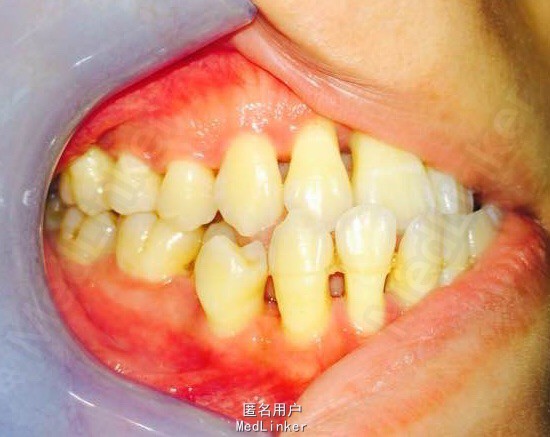

女,23岁,重度侵袭性牙周病,有家族遗传性

讨论:牙周治疗处于维护稳定阶段,下合2—2牙槽骨吸收至根尖1/3水平,是否适合正畸?下个前牙的保留问题